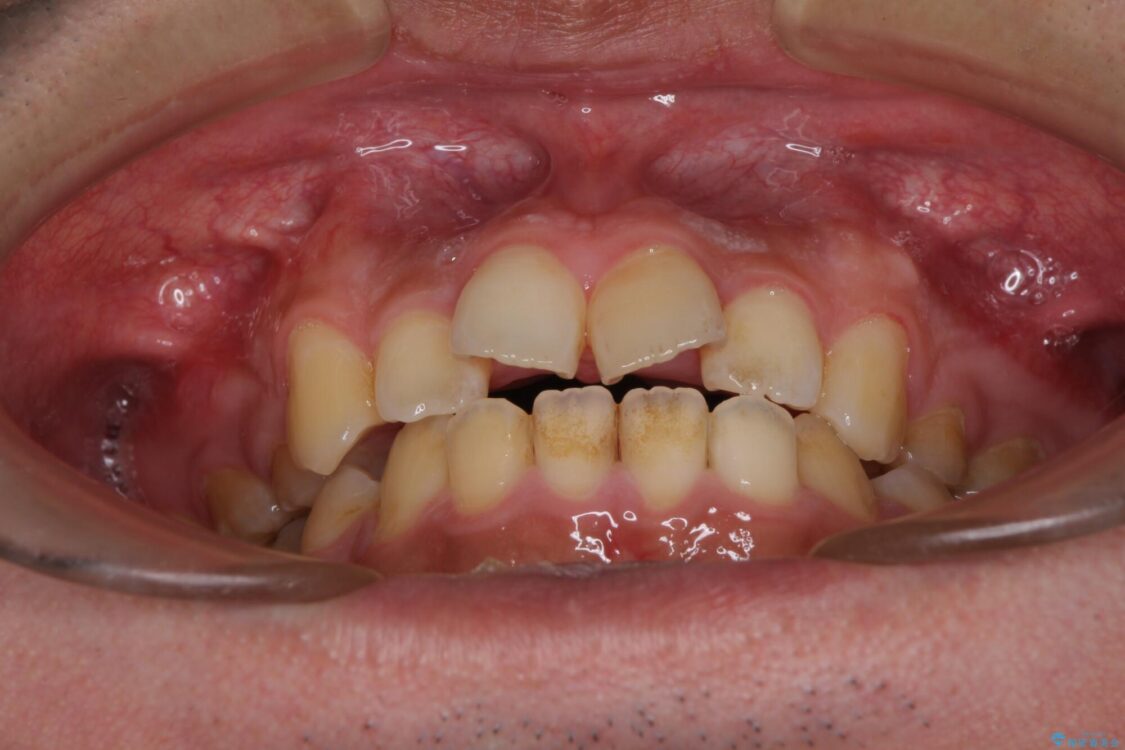

高校時代に行った抜歯矯正が後戻りをしたとのことで来院された患者様です。

再矯正であることから、目立ちにくい装置を希望されたため、インビザラインにて矯正治療を行うこととしました。

治療前

• 後戻りでデコボコの前歯 インビザライン矯正治療 治療前画像